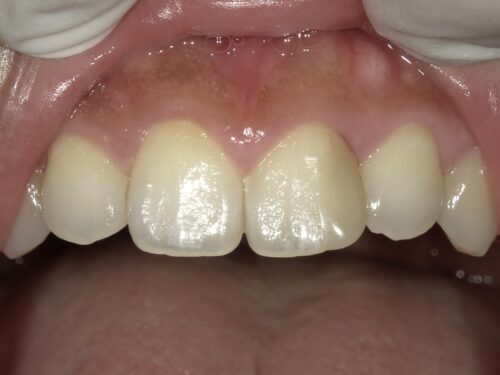

あとは、この前歯の端っこの古くなったコンポジットレジンを、

削りとって、

新しい白いコンポジットレジンで詰め直します。

どうでしょうか。

それぞれの段階で見比べてみましょう。

コンポジットレジン後

詰め物を新しくした後は全体が白くなって、かつ、前歯のところも違和感がないですよね。